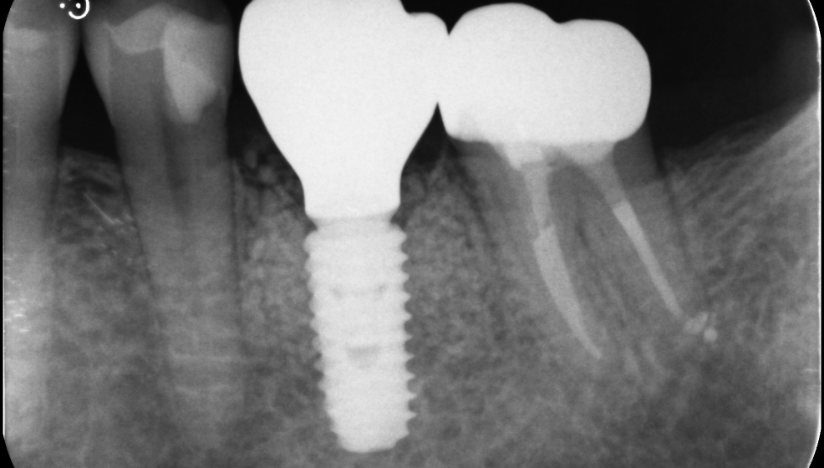

主訴

奥歯で噛めない、歯茎が腫れてきた

治療内容

抜歯即時インプラント埋入1本、待時インプラント埋入2本、リッジプリザベーション(顎堤温存術)、GBR

治療期間

6〜8ヶ月

治療費用

1,947,000

治療の

リスク

オッセオインテグレーションが得られなかった場合、撤去、再度埋入の可能性